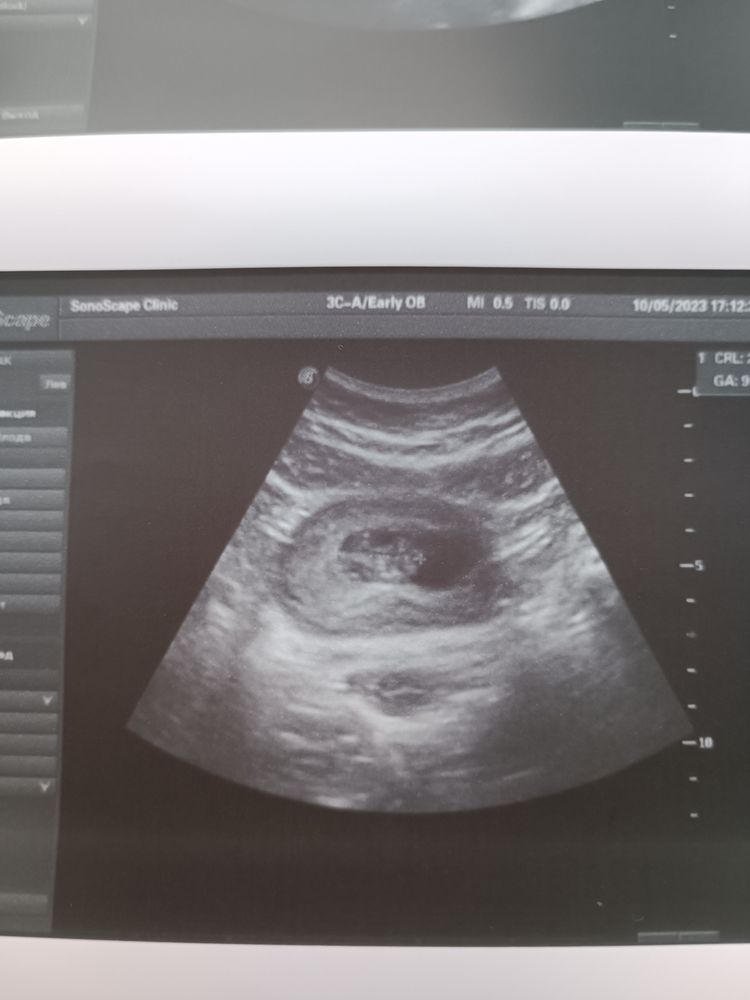

Всё хорошо, узи с моно моно 10 недель💞

Ирина Витальевна , у Вас получается, моно-моно? Перегородку не увидели?

Евгения , всё в порядке, но на перегородку еще надеюсь) Спасибо и вашим малышам тоже💖💗